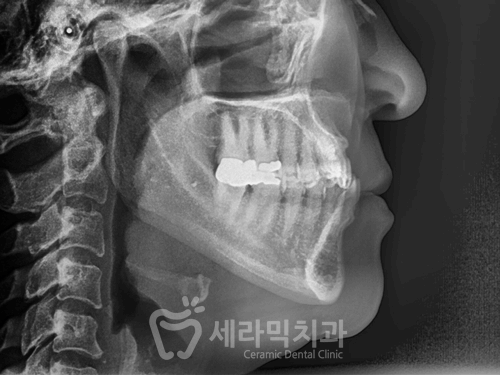

(2) 문제점 분석, 진단

① 치열불규칙

② 앞니 반대교합

③ 아래턱 돌출 경향

③ 아래턱 돌출 경향 개선 효과

※ 돌출된 턱 자체를 뒤로 밀어넣은 것은 아닙니다.

안쪽으로 밀려들어가있던 위쪽 치아와 잇몸이

치아교정을 통해 균형잡힌 위치로 이동을 하면서

인중에서 입술로 이어지는 라인과

윗 입술이 볼륨감이 생겼고,

아래 잇몸의 돌출 경향이 개선된 효과가 나타납니다.